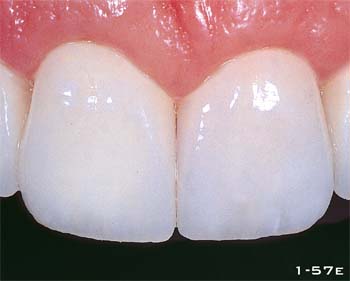

Abb. 1-57e Nahaufnahme der definitiven Versorgung.